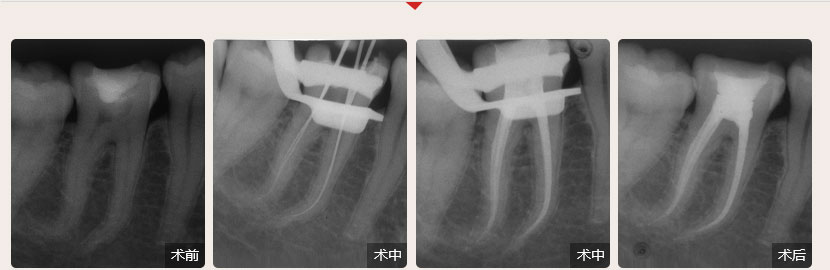

德倫口腔醫(yī)生全國根管治療技術(shù)競賽獲獎案例展示

根管治療過程